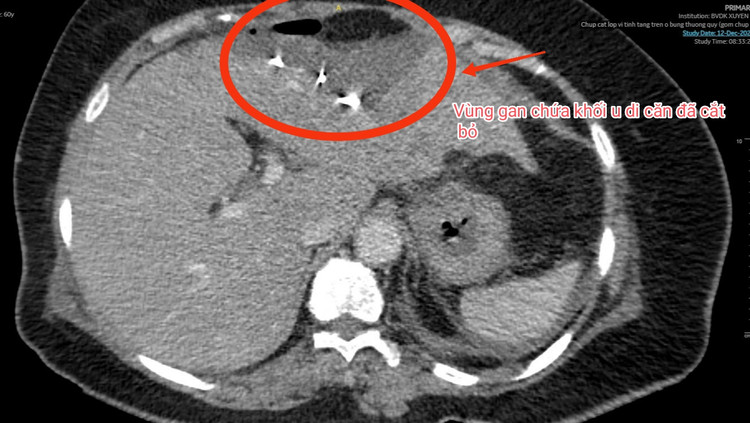

| Ảnh khối u di căn gan đã được cắt bỏ trên phim chụp |

Tại khoa Ngoại Tổng Quát BVĐK Xuyên Á, các bác sĩ đã thăm khám, thực hiện các cận lâm sàng và ghi nhận hậu môn nhân tạo đại tràng sigma thông tốt, trên hình ảnh MSCT cho thấy một tổn thương di căn tại hạ phân thùy II và III của gan với kích thước khối u 2x3 cm.